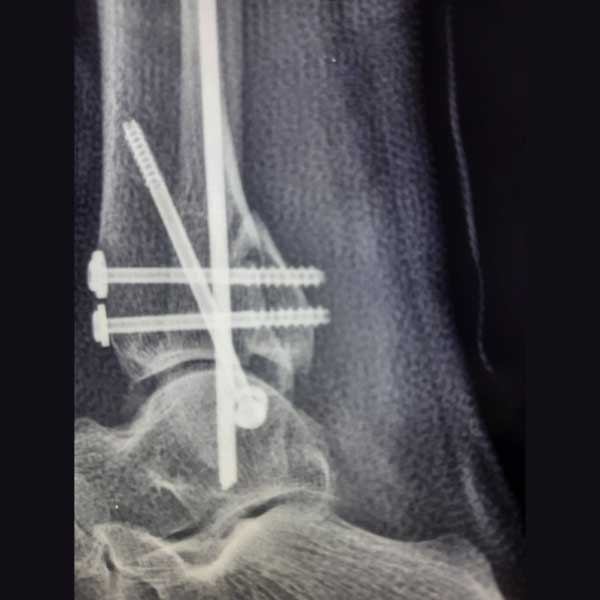

Case:19 Percutaneous fixation with Implants

A male patient, aged 78 years had been diagnosed to have a closed Pott’s fracture Left Ankle. He was treated operatively with Percutaneous fixation with Implants.

Pre-Operative

Post-Operative